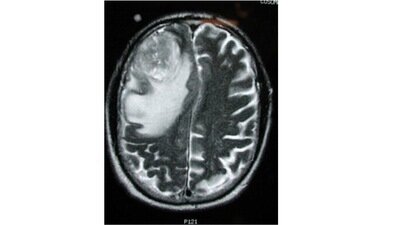

my mom won’t get to see me grow up. Recently, my mum was diagnosed with a Glioblastoma, a grade 4 brain tumour that is not only extremely aggressive but also terminal. Her tumour developed in the speech center of her brain, causing it to swell and impair her ability to communicate. For several weeks, she struggled to speak, her words turning into gibberish. It also affected her memory, to the extent that she didn't recognize me, her own daughter, She's undergone brain surgery and currently endures double chemotherapy every month, fighting hard against a condition with so few treatment options. I am a minor and have had to learn how to pay bills, work out legal issues as a power of attorney and realise that my mom won’t get to see me grow up and won’t be there for all the milestones in my life. I don’t have a father as I was born from IV so I will be living with my grandma who is very elderly. I don’t want to loose my mom, she is the only person who has stuck by my side when I was physically bullied and abused at school and when I was going through a really hard time mentally a while back.

Glioblastoma is a devastating diagnosis, not just for those who suffer from it, but also for their families. It is the most common and deadliest form of brain cancer, with an average survival rate of just 12 to 15 months. Current treatment options are limited, mostly focusing on prolonging life rather than offering a cure. The situation is dire and demands urgent attention.